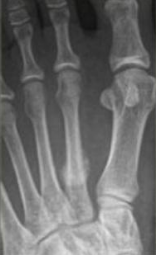

骨巨细胞瘤

是一种局部侵袭性肿瘤,大部分为良性,部分生长活跃,也有少数一开始就是恶性

男女发病率相近,好发年龄是20-40岁

膨胀性多房性偏心性骨破坏,横向生长

分房状或皂泡状,骨破坏区无钙化和骨化影

24Y,M

手足短骨解剖及常见疾病的影像学表现“左足第一跖骨肿物”:骨巨细胞瘤,肿瘤浸润骨皮质及软组织,伴反应性骨壳形成